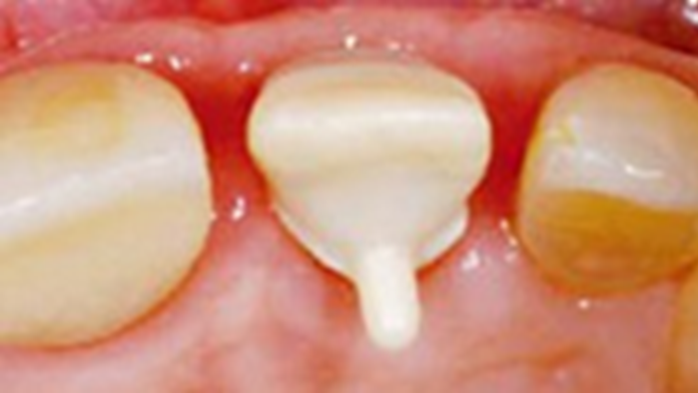

Clinical case: Replacement of fractured central incisor (#11) with immediate implant

& Root Membrane Technique

- Courtesy of Dr. Miltiadis Mitsias, Greece -

AnyRidge, Root Membrane Technique, retrospective study, long-term study, immediate implants, bone resorption, bone preservation, Dr. Miltiadis Mitsias,survival, success, maxillary anterior, single replacement

AnyRidge implant system, Root Membrane kit

The Root Membrane Technique: A retrospective clinical study with up to 10 years of follow-up./Implant Dent. 2018 Oct;27(5):564-574

https://www.ncbi.nlm.nih.gov/pubmed/30161062